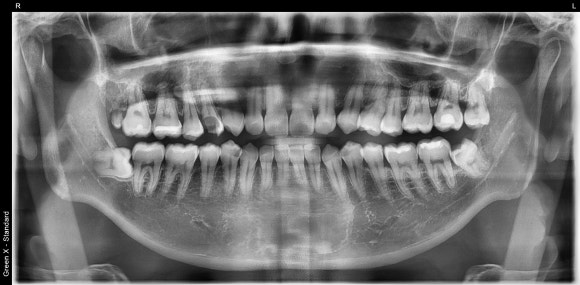

20250402

충치를 제거하니 보이는 신경조직.

치아는 이제 껍데기만 남았군요.

놀랍게도 단단한 치아 내부에는 말랑말랑한 신경과 혈관조직이 있습니다.